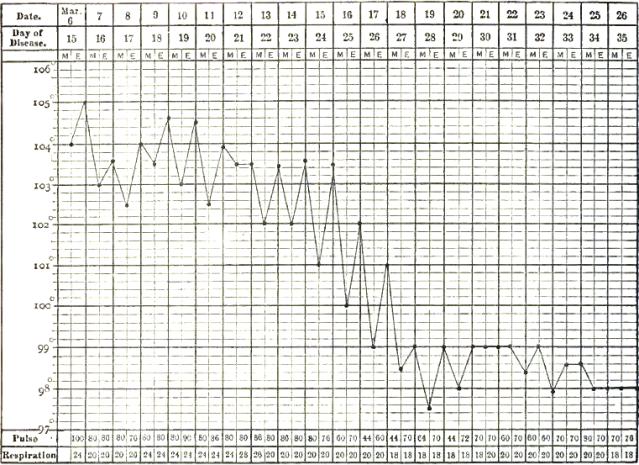

| 13. | CHART SHOWING RECRUDESCENCE OF FEVER FROM INDISCRETION OF DIET |

| 14. | CHART SHOWING FALL OF TEMPERATURE FROM INTESTINAL HEMORRHAGE IN TYPHOID FEVER |

| 15. | PULSE-TRACING IN RELAPSES OF TYPHOID FEVER |

| 16. | CHART OF TEMPERATURE IN TYPHOID FEVER WITH RELAPSE.—ORIGINAL ATTACK |

| 17. | CHART OF TEMPERATURE IN TYPHOID FEVER WITH RELAPSE.—RELAPSE |

| 18. | TEMPERATURE CHART OF TYPHOID FEVER.—ABORTIVE ATTACK, FOLLOWED BY TYPICAL ATTACK |